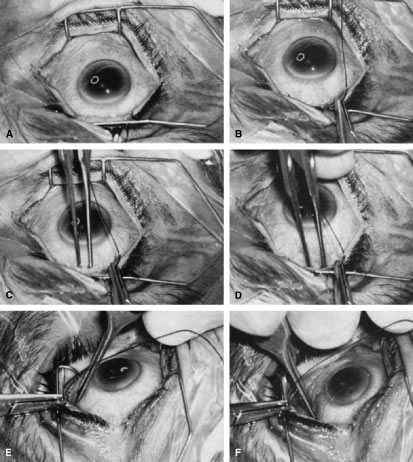

is paid to bringing it into view.   Fig. 14. Placement of a superior rectus muscle bridle suture. A. The eye with a Barraquer-Colibri speculum in place. The superior rectus

muscle is well hidden by the upper lid (lower portion of photograph). B. The needle of a single-armed 4-0 black silk suture is used to retract

the upper lid, allowing better visualization of the area in which the

superior rectus suture is to be placed. C. The tips of a Lister forceps are held tangential to the superior portion

of the globe, approximately 2 mm apart. D. The forceps are moved superiorly so that the tips extend past the insertion

of the superior rectus muscle, about 12 mm superior to the lumbus. E. Side view showing the lid held superiorly by the needle of the 4-0 black

silk suture and the Lister forceps in its initial position. F. The handle of the forceps is rotated superiorly while the tips are pressed

firmly against the globe. The indentation of the globe is caused

by the pressure of the forceps. When the forceps have been rotated to

the position shown, the tips are closed around the superior rectus muscle. G. After the muscle has been grasped firmly, the forceps are again rotated

inferiorly and the globe is pulled inferiorly. H. Surgeon's view of the proper grasp of the superior rectus muscle. I. The needle of the 4-0 black silk suture is placed under the superior rectus

muscle not through its belly. J. Proper position of the needle, deep to the forceps and between the globe

and the superior rectus muscle belly. (Spaeth GL. Glaucoma surgery. In Spaeth GL (ed). Ophthalmic Surgery: Principles

and Practice. Philadelphia: WB Saunders, 1990.) Fig. 14. Placement of a superior rectus muscle bridle suture. A. The eye with a Barraquer-Colibri speculum in place. The superior rectus

muscle is well hidden by the upper lid (lower portion of photograph). B. The needle of a single-armed 4-0 black silk suture is used to retract

the upper lid, allowing better visualization of the area in which the

superior rectus suture is to be placed. C. The tips of a Lister forceps are held tangential to the superior portion

of the globe, approximately 2 mm apart. D. The forceps are moved superiorly so that the tips extend past the insertion

of the superior rectus muscle, about 12 mm superior to the lumbus. E. Side view showing the lid held superiorly by the needle of the 4-0 black

silk suture and the Lister forceps in its initial position. F. The handle of the forceps is rotated superiorly while the tips are pressed

firmly against the globe. The indentation of the globe is caused

by the pressure of the forceps. When the forceps have been rotated to

the position shown, the tips are closed around the superior rectus muscle. G. After the muscle has been grasped firmly, the forceps are again rotated

inferiorly and the globe is pulled inferiorly. H. Surgeon's view of the proper grasp of the superior rectus muscle. I. The needle of the 4-0 black silk suture is placed under the superior rectus

muscle not through its belly. J. Proper position of the needle, deep to the forceps and between the globe

and the superior rectus muscle belly. (Spaeth GL. Glaucoma surgery. In Spaeth GL (ed). Ophthalmic Surgery: Principles

and Practice. Philadelphia: WB Saunders, 1990.)